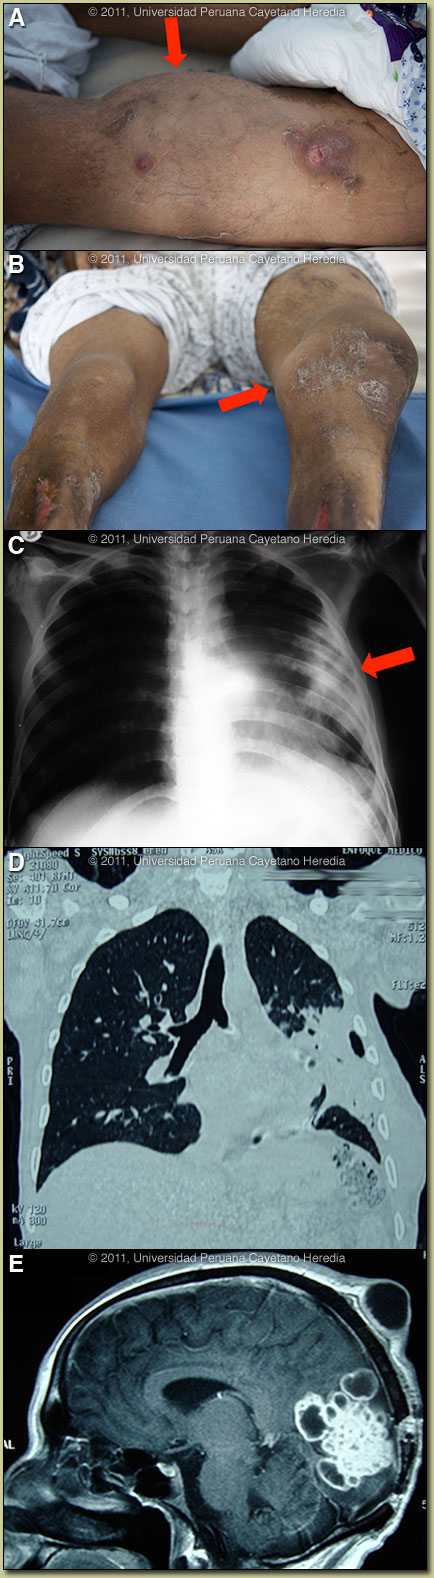

| Diagnosis: Disseminated nocardiosis. |

Discussion: An aspirate of a right forearm abscess grew a weakly acid-fast organism compatible with Nocardia species when cultured aerobically [Images F, G]. Further workup is in progress. In addition, as aspirate of the knee joint grew Nocardia. The culture was negative for mycobacteria and did not grow anaerobically. Review of the images indicated that both the scalp and chest-wall lesions were contiguous with internal foci of infection. The brain MRI is highly diagnostic of nocardiosis.

Although literature is limited, nocardiosis appears to present in the tropics in a similar way to non-tropical areas, though this is the first case we have seen in over 20 years in our tertiary care facility in Lima. Although M. tuberculosis infection would be at the top of the differential diagnosis list in the tropics at initial pulmonary presentation in this case, the spread to skin, joint and CNS would be unusual. Actinomycosis rarely presents in the CNS and actinomycotic skin lesions arise entirely by contiguous spread usually from a respiratory focus and that would not explain the hematogenous spread to the knee joint here. Endemic fungi (sporotrichosis, paracoccidioidomycosis) can present with skin nodules but these quickly ulcerate and would not remain nodular over a period of years. Some uncommon disseminated forms of L. brasiliensis exist but would not have pulmonary or CNS manifestations. Nocardia are aerobic, partially acid-fast, branching, filamentous, slow growing Gram-positive bacilli. Infection is acquired by direct inoculation or inhalation and spreads hematogenously from the lungs. Six basic forms of disease reported: pulmonary, systemic, central nervous system (rare), extrapulmonary, cutaneous, and actinomycetoma (often presenting as ‘madura foot’ in the tropics). Nocardiosis is mostly seen in severely immunosuppressed patients such as with HIV, organ transplantation, corticosteroid therapy, autoimmune conditions, COPD, and malignancy. TMP/SXT prophylaxis as used with many of these patients for a number of other infections does not seem highly protective against nocardiosis. The great majority of patients have a risk factor; our patient had a long history of alcoholism and incarceration. There are no therapeutic recommendations based on clinical trials. Usually, TMP/SMX is the primary choice for brain abscesses. For the disseminated form, as here, intravenous therapy should be for at least 2 months with at least 2 drugs, and with 3 drugs if there is CNS involvement. Our patient is now improving on TMP/SMX plus a third generation cephalosporin plus Amikacin. The plan is to complete oral therapy for at least 1 year.